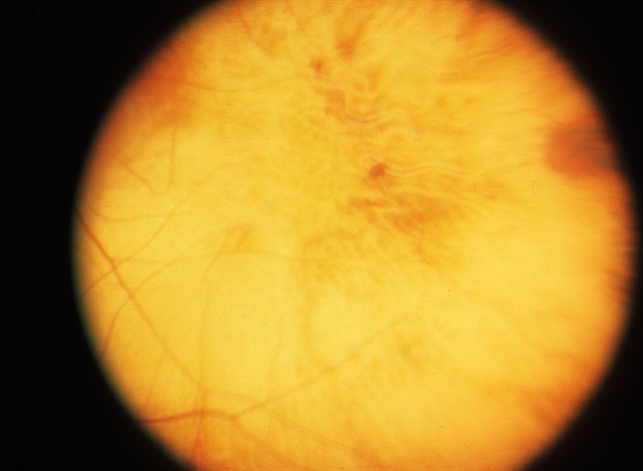

Choroideremia

Choroideremia.